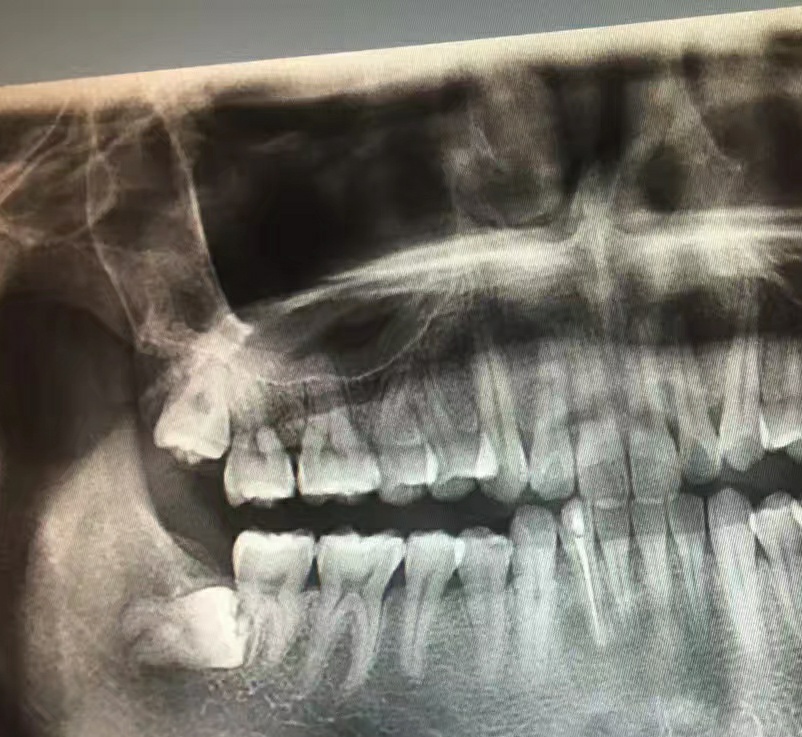

医生先让拍牙片,看看你的牙长成啥样,好决定怎么动手除掉它哈哈

而我也很“幸运”,是这种,水平阻生,必须经此一役战胜它。也是这一次,让我知道了我有多富,4颗智齿。然后开单去拿麻药,大战一触即发!